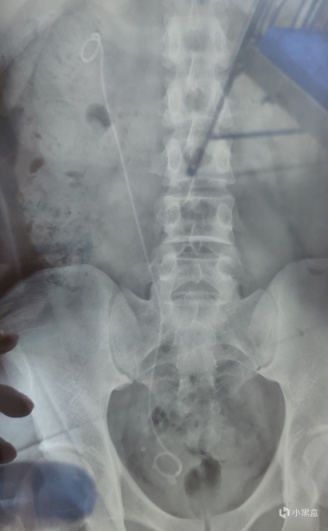

果不其然,X光片中顯示,體內有一條大約15mm*5mm的長條結石,現在正停留在輸尿管末端,大概已經堵住了那半邊,右腎也出現了輕度積水。醫生建議我儘快手術,還給了我一張名片,讓我隨時聯繫他。

片子裏能清楚地看到那根雙J管